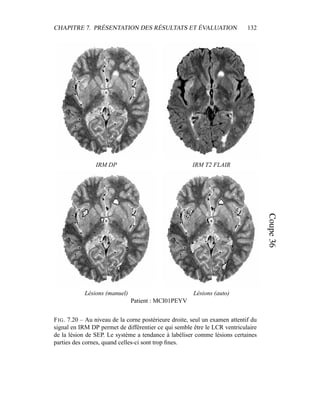

CHAPITRE 8. DISCUSSIONET PERSPECTIVES 165 Lésions (manuel) Lésions (auto.) IRM DP IRM T2 FLAIR Patient : MCI02 FIG. 8.13 – La lésion de SEP présente sur la partie antérieure gauche de ces coupes est connexe au LCR cortical ; elle est donc considérée comme faisant partie de l’extérieur du cerveau, ce qui explique les faux négatifs sur cet image. La présence de ce qui semble être une résection chirurgicale ne facilite pas le contourage de cette zone.

• 175.

CHAPITRE 8. DISCUSSIONET PERSPECTIVES 166 8.2.4 Lésions de la fosse postérieure Lors de cette étude et de la présentation des résultats au chapitre précédent, les lésions de la fosse postérieure ont été écartées. La chaîne de traitements n’est ici pas appropriée, car ces lésions sont détectables en IRM DP (figure 8.14) mais pas en IRM T2 FLAIR. Les lésions ont par contre un signal proche de celui de la matière grise en IRM DP ; l’intensité ne peut pas être utilisée seule comme critère de détection. Dans ce cas, une piste pourrait être d’obtenir dans un premier temps un masque de ce que serait la matière blanche s’il n’y avait pas de lésions. Un recalage non-rigide ou l’application d’un modèle déformable sur la matière blanche du cervelet sont plusieurs pistes à explorer : il suffit alors d’extraire les lésions comme des points aberrants dans cette zone ne devant contenir que de la matière blanche. Des lésions sont également visibles dans le tronc cérébral : ces lésions sont importantes car comme les lésions dans le cervelet, elles sont souvent associées à une atteinte physique définitive. Ces lésions sont très difficiles à voir, et la non- uniformité du signal dans cette zone ne facilite pas la lecture des images. 8.3 Conclusion Nous avons ici regardé les lésions en fonction de leur type : périventriculaire, juxtacorticale, corticale et fosse postérieure avec le cas particulier des trous noirs. Ce classement correspond à une réalité médicale, car ces différentes catégories de lésions sont utilisées dans les critères de diagnostic et dans l’observation de la maladie. Dans le cadre de cette évaluation, la catégorisation de ces lésions a été effectuée à la main et de manière arbitraire. Il serait intéressant de définir une caractérisation précise de ces catégories à l’aide de quantificateurs – signal, taille, position, localisation par rapport à certaines structures cérébrales. L’automatisa- tion de cette caractérisation permettrait l’extraction automatique des critères de Barkhof, mais aussi de pouvoir explorer de nouveaux algorithmes de segmenta- tion spécifiques à chaque catégorie : segmenter chaque type de lésion de manière différente semble indispensable pour obtenir des résultats plus homogènes.

• 176.